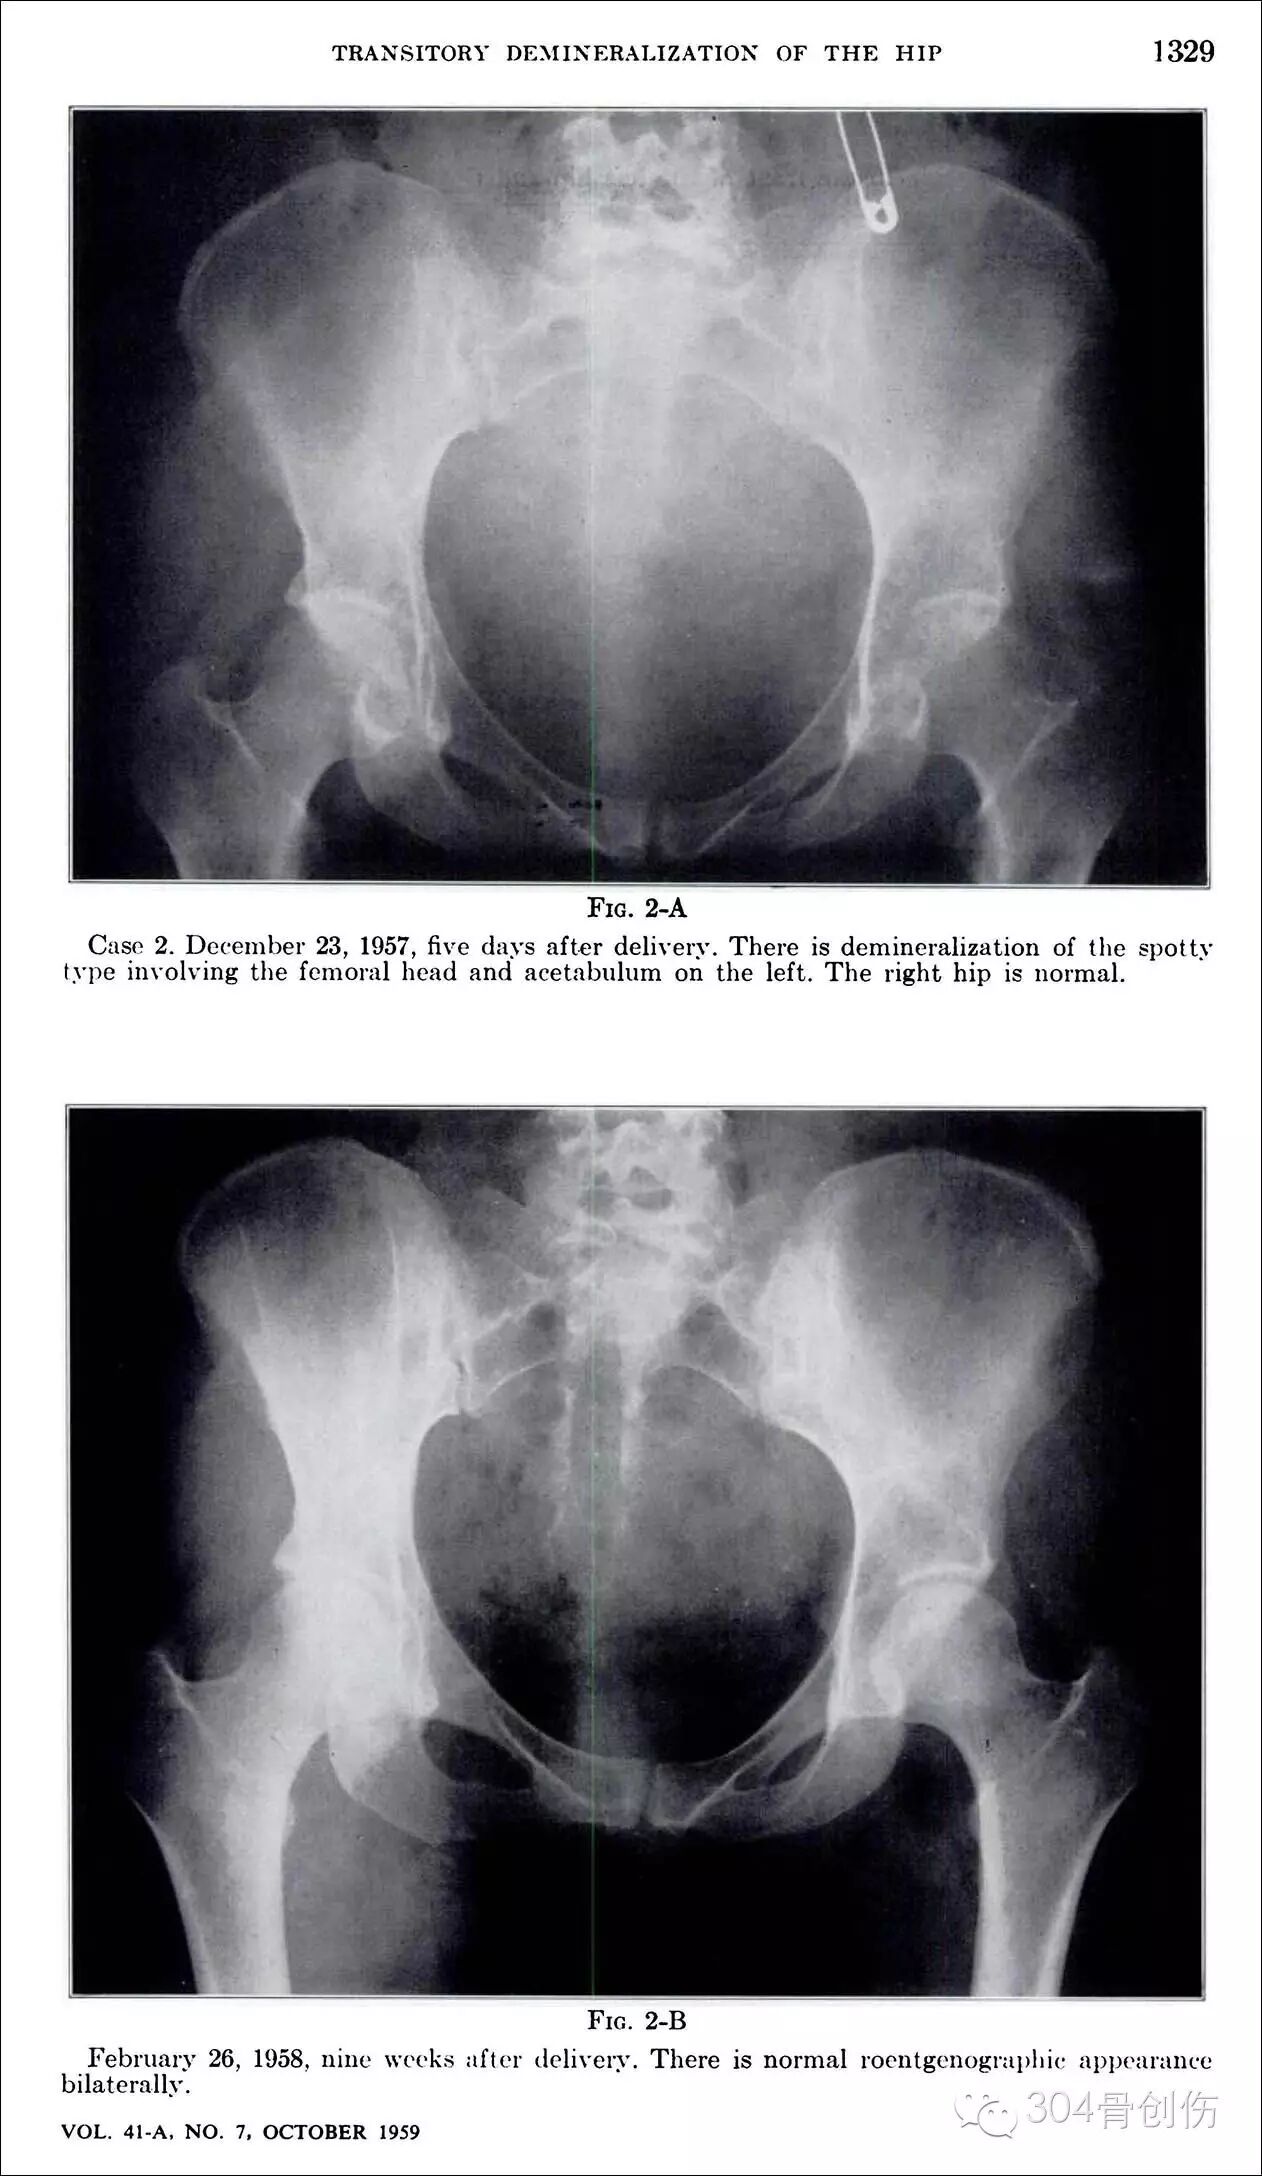

髋部一过性骨质疏松症(transient osteoporosis of the hip, TOH)是出现于妊娠晚期的一种罕见的骨代谢紊乱状况,其病因不清楚,表现为髋部疼痛及活动受限,可在髋关节X线上观察到明显骨量减少,1959年Curtiss教授首次报道(图),2005年国内郭依廷医生首次报道(图),综合发病过程,定义为“妊娠期一过性骨质疏松症”,不完全统计:全世界报道大约100余例,多为脊柱骨折,双侧股骨颈骨折少见,陈旧股骨颈骨折处理极为困难,目前缺乏大宗相关文献报道。

怀孕期间会骨折吗?-怀孕期

图-1959年Curtiss首次报道

1.Curtiss PH Jr, Kincaid WE. Transitory demineralisation of the hip in pregnancy. A report of three cases. JBJS(A),1959 ; 41: 1327~1333.